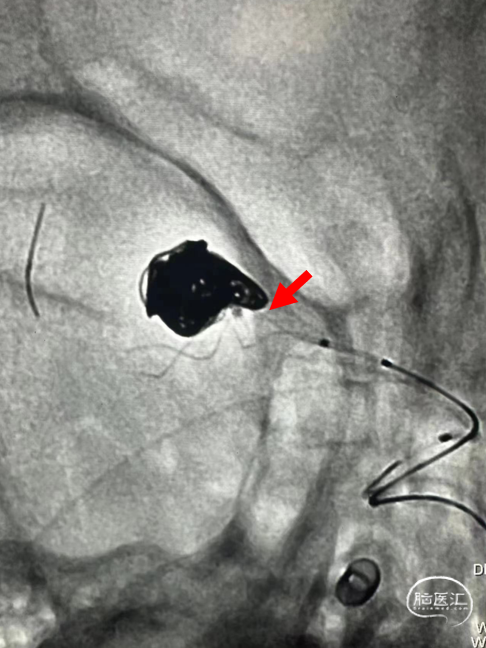

故半释放一枚LEO Baby 2.5*18mm支架,在瘤颈处进行推挤呈“灯笼”状;

再依次置入6*20cm、4*10cm、2*6cm三枚弹簧圈,全释放支架,完成治疗。

术后可见,通过支架的推挤“修饰”瘤颈,完美保留M2段下干支;各分支血管血流通畅。